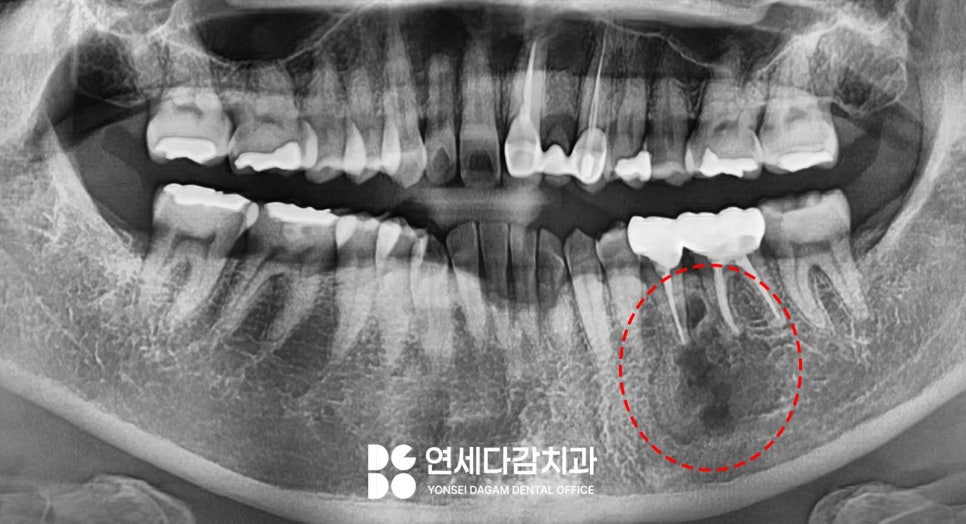

정기 검진을 시행하는 과정에서

어금니 부위에 경계가 불분명한 병소를

발견하였습니다.

이런 형태는 법랑모세포종으로

의심되었습니다.

거여동 치과 에서도 발견 당시

특별한 불편감은 없었으나,

경계가 불분명한 병소의 경우

상급병원에서 조직 검사를 받아,

이상이 있는지 확인해 보는 것이 좋다고

판단하여 의뢰를 했습니다.

거여동 치과 에서 의뢰한 결과

조직 검사 후 법랑모세포종이 맞다는

진단이 나왔습니다.